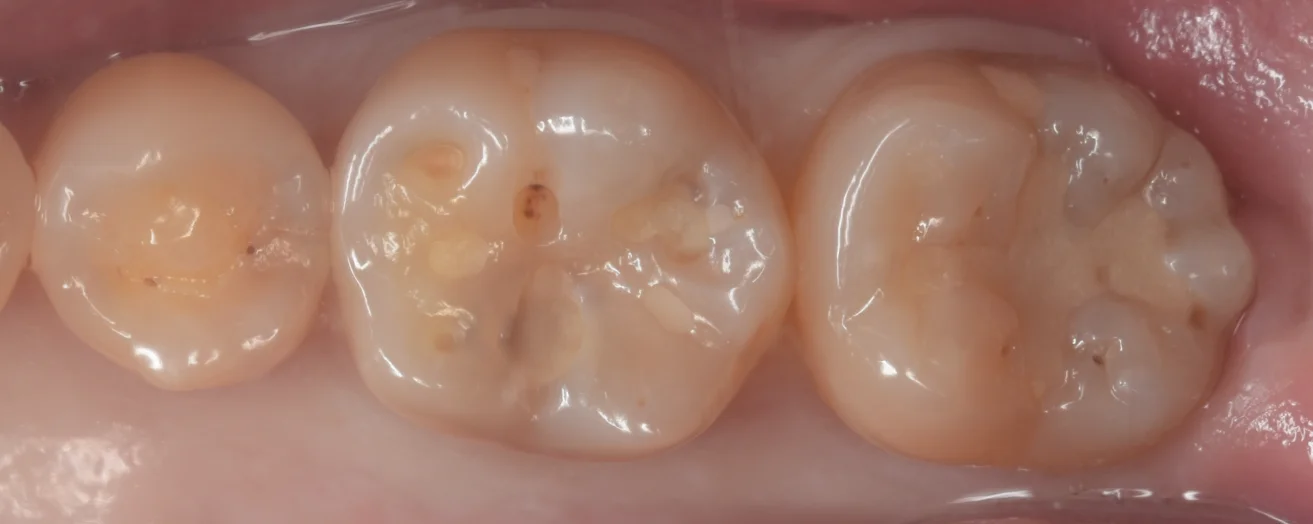

まずは術前からです。

小学生の頃に治したというコンポジットレジンが入っています。

やはり20年近く前のものですから安定性がイマイチなのか劣化が激しいですね。

一部脱離しているところもあります。

また透けて内部に虫歯があるのも非常にわかりやすくなっていますね。

一番左の歯については後ろの歯との間にクラック(亀裂)が入っているのがわかります。

虫歯を見えやすくしたのがこちらです。